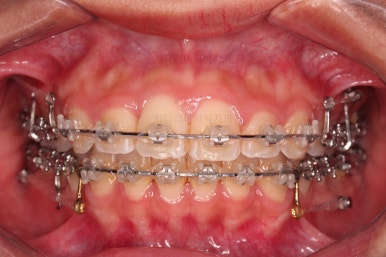

이번 환자분이 선택한 장치는 엠파워 클리어라고 하는 자가결찰 세라믹 장치입니다.

흔히들 아시는 클리피씨 장치와 동일한 종류의 장치인데, 제조국이 일본(클리피)이냐 미국(엠파워)이냐의 차이가 있습니다.

장치 부착 직후의 얼굴 모습입니다.

장치가 주는 느낌과 장치를 부착해서 변하는 입매의 느낌 참고 바랍니다.